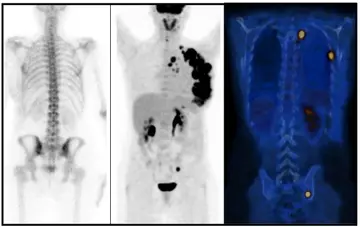

خودآزمایی: تشخیص شماچیست؟

یک خانم ۷۵ساله‌ باسابقه ۳ماهه احساس ضعف و خستگی تدریجی مراجعه‌کرده است.